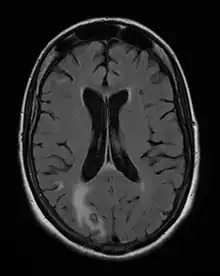

On décrit de rares cas où un sujet VIH+, sans immunité anti-toxoplasmique (pas de contact antérieur) contracte une toxoplasmose, mais le plus souvent il s'agit de patients immunisés contre la toxoplasmose, donc porteurs de kystes qui réactivent l'infection lors d'une baisse conséquente de leurs défenses immunitaires ; généralement, ils présentent une toxoplasmose cérébrale.

La toxoplasmose cérébrale est une maladie opportuniste dont la survenue chez les personnes séropositives marque l'évolution de l'infection par le VIH au stade de sida. Elle survient en règle générale chez des sujets séropositifs au VIH, ayant moins de 200 lymphocytes T CD4+, avec une sérologie toxoplasmique positive et ne recevant pas de prophylaxie spécifique. C'est alors que les bradyzoïtes libèrent les tachyzoïtes qui essaiment dans tout le corps via le système sanguin[37]. En 2008 en France, la toxoplasmose cérébrale représentait 12 % des personnes qui découvraient leur séropositivité au VIH après le déclenchement d'une affection opportuniste[38].

Les symptômes de début peuvent être insidieux, céphalées d'installation récente ou réactivation de céphalées anciennes, avec ou sans fièvre. Trois situations sont possibles :

- il s'agit d'un (ou de plusieurs) abcès cérébral (cas le plus fréquent) donnant un tableau neurologique rapidement progressif. Les signes cliniques dépendent de la localisation de(s) l'abcès : hémiplégie ou hémiparésie, syndrome cérebelleux, aphasie, amputation du champ visuel, ou signes plus diffus à type de somnolence, désorientation, crises comitiales ;